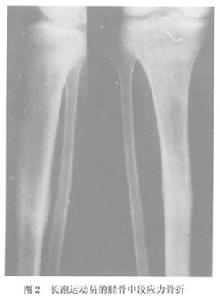

在體育運動和軍事訓練中,應力骨折最常見的部位是脛骨,多數報導占所有應力骨折的半數以上,劉大雄報導占78.0%,黃昌林報導達83.3%。脛骨應力骨折的發病部位因運動項目的不同而各異,行軍訓練的新兵群體多發生在近段脛骨的後內側,中長跑運動員好發於脛骨中下段的後側,而芭蕾舞演員則多發生在脛骨中段的前側。

其他輔助檢查:X 線片早期無陽性發現,但長期堅持訓練者,X 線片上可顯示應力性骨折。